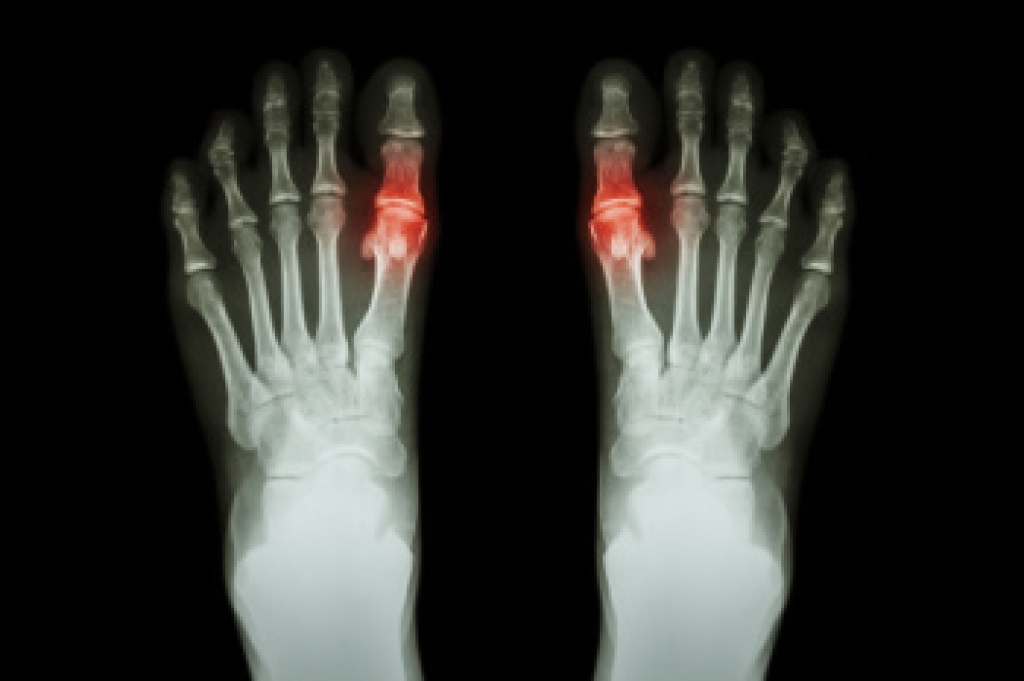

Ingrown toenails occur when a toenail grows sideways into the bed of the nail, causing pain, swelling, and possibly infection.